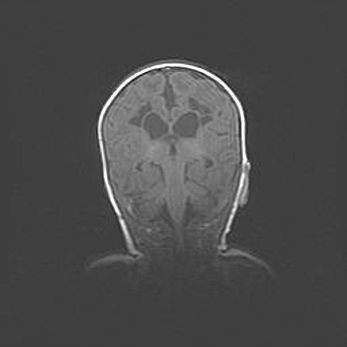

Наружная гидроцефалия с возможной атрофией височных областей.

Возраст: 28 дней

Вес: 3670 г

Пол: мужской

Окружность головы: 38 см

Срок гестации: 40 недель

Гидроцефалия головного мозга у новорожденных – это заболевание, которое характеризуется скоплением избыточного количества спинномозговой жидкости в желудочковой системе головного мозга в результате затруднения её перемещения от места выработки к месту поглощения в кровеносную систему или вследствие нарушения абсорбции. При открытой наружной форме гидроцефалии у новорожденных расширяются и переполняются субарахноидные пространства.

При нормотензивных  формах,  которые,  как  правило,  являются  следствием  перенесенных ишемических  повреждений  паренхимы  мозга,  возможно  сочетание микроцефалии  с нормотензивной гидроцефалией. В основе данных изменений лежит атрофия больших полушарий с преимущественной  локализацией  в  лобно-височных  областях.